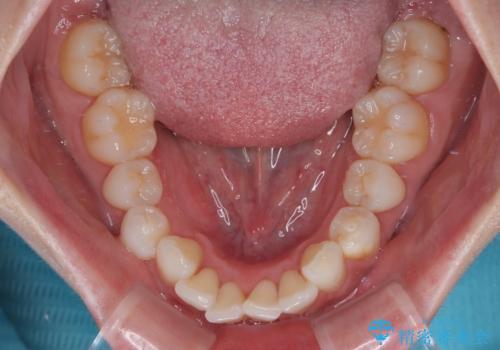

- 上下前歯の叢生を気にして来院された患者様です。

軽度な叢生であり、安価で短期間の治療を規模されていたため、インビザライン・モデレートを用いて矯正治療を行うこととしました。

インビザライン・モデレートは、製作できるアライナーの枚数に制限があるため、移動可能な量に限りがあるものの、インビザライン・ライトよりも枚数が多いため、幅広い症例に対応可能です。